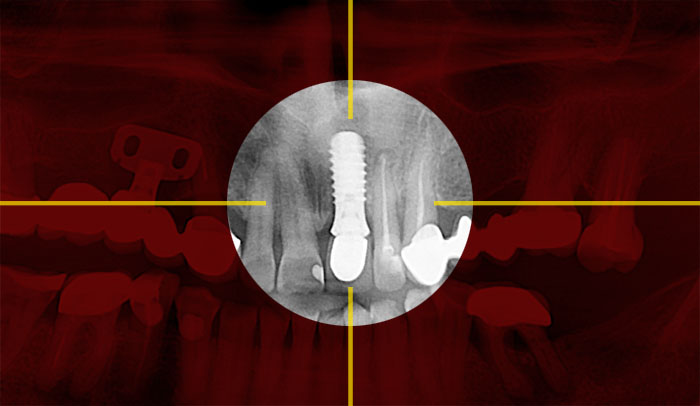

Контрольная рентгенограмм через 15 лет после операции. Если на рентгенограмме и можно различить небольшую щель между имплантатом и костью на уровне полированной части имплантата, то клинически она полностью отсутствует и не диагносцируется парадонтологическим зондом.